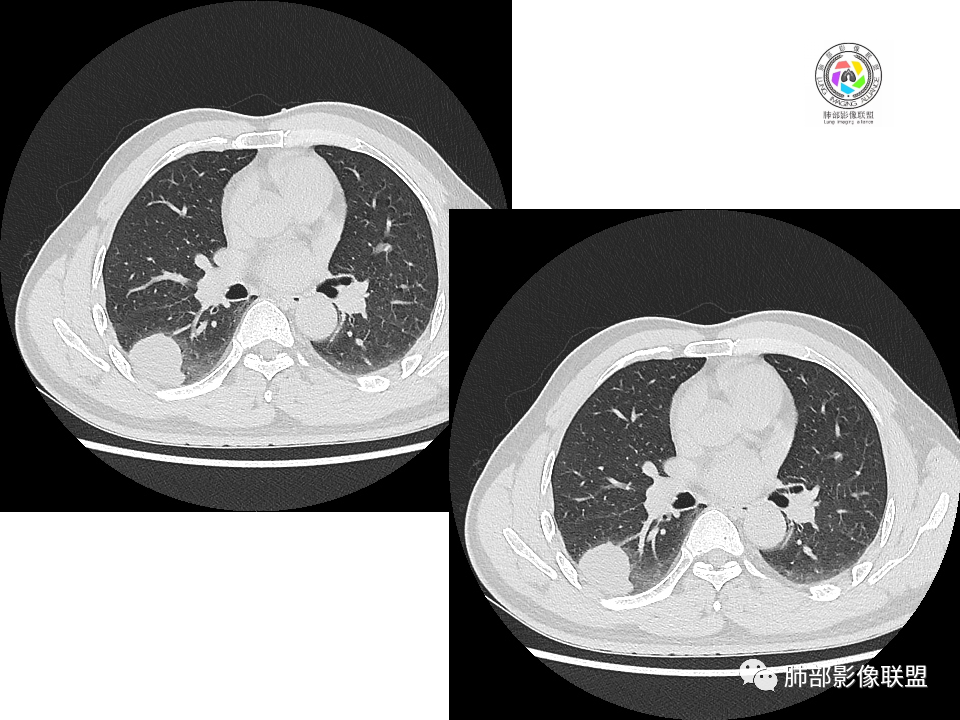

右肺中叶病灶

GGO,与支气管关系密切

这个形态、与支气管关系,与前两个不一致,所以考虑独立炎性病变。

3.右肺中叶外侧段胸膜下散在小片影,磨玻璃密度为主,边界不清,支气管相关。符合炎性特征!

显然本例焦点在于背段那个边缘光整的块影!